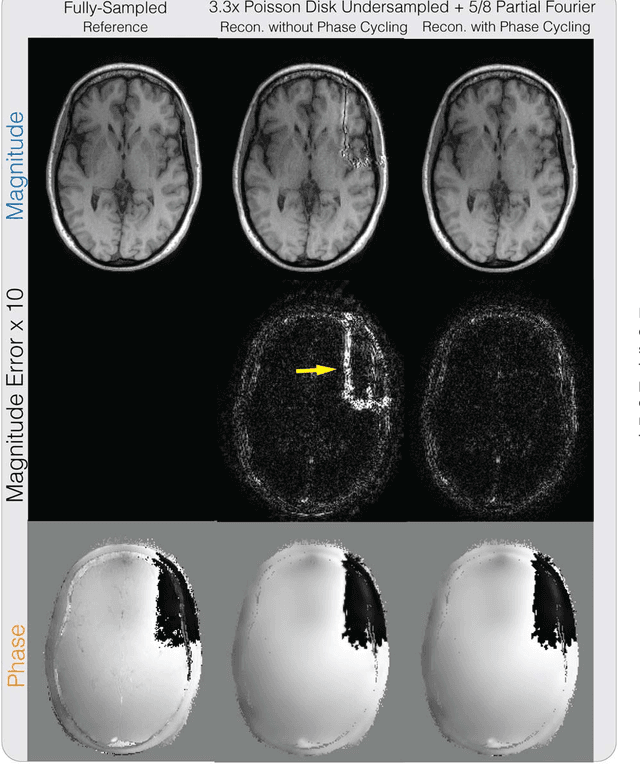

Abstract:Purpose: To develop a general phase regularized image reconstruction method, with applications to partial Fourier imaging, water-fat imaging and flow imaging. Theory and Methods: The problem of enforcing phase constraints in reconstruction was studied under a regularized inverse problem framework. A general phase regularized reconstruction algorithm was proposed to enable various joint reconstruction of partial Fourier imaging, water-fat imaging and flow imaging, along with parallel imaging (PI) and compressed sensing (CS). Since phase regularized reconstruction is inherently non-convex and sensitive to phase wraps in the initial solution, a reconstruction technique, named phase cycling, was proposed to render the overall algorithm invariant to phase wraps. The proposed method was applied to retrospectively under-sampled in vivo datasets and compared with state of the art reconstruction methods. Results: Phase cycling reconstructions showed reduction of artifacts compared to reconstructions with- out phase cycling and achieved similar performances as state of the art results in partial Fourier, water-fat and divergence-free regularized flow reconstruction. Joint reconstruction of partial Fourier + water-fat imaging + PI + CS, and partial Fourier + divergence-free regularized flow imaging + PI + CS were demonstrated. Conclusion: The proposed phase cycling reconstruction provides an alternative way to perform phase regularized reconstruction, without the need to perform phase unwrapping. It is robust to the choice of initial solutions and encourages the joint reconstruction of phase imaging applications.